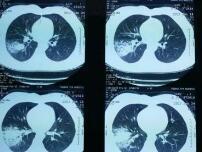

支原体肺炎患者胸部X线检查变化很大,病变可很轻微,也可很广泛。体征轻微而胸片阴影显著,是本病特征之一。血常规检查白细胞高低不一,大多正常,有时偏高。

支原体肺炎的临床表现和胸部X线检查并不具特征性,单凭临床表现和胸部X线检查无法做出诊断。若要明确诊断,需要进行病原体的检测。国内支原体肺炎的诊断主要依靠血清学检测。